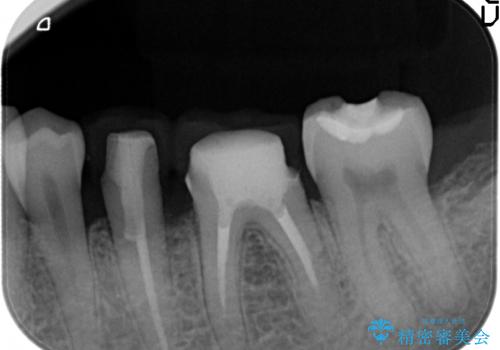

銀歯の下には再発した虫歯やセメントの漏出が見られ、丁寧に除去したのちセラミックによるクラウン・ブリッジ補綴を行います。

適合や精度の悪い銀歯は、時間の経過とともに虫歯の再発リスクが高まります。